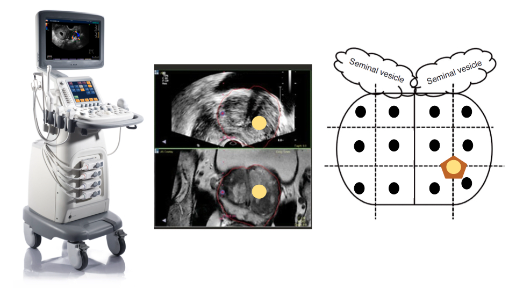

Технологическое развитие медицинского оборудования привело к возможности совмещения снимков МРТ и УЗИ; такая технология получила название «фьюжн». Это позволяет, при наложении друг на друга и синхронизации МРТ-изображения и ультразвукового изображения, произвести точечный забор материала из подозрительного фокуса, диагностированного на МРТ. Информативность такого исследования значительно превосходит информативность стандартной методики и снижает вероятность получения ложноотрицательных результатов.

Кроме точного выявления опухоли, фьюжн-биопсия простаты позволяет выявить тот самый агрессивный, клинически значимый рак простаты (Глисон 7 и более), что повлияет на выбор единственно правильной тактики лечения.

Скрининг и первичная диагностика рака простаты лежат в основе раннего выявления и выбора единственно правильного метода лечения. На протяжении многих лет перед специалистами стояла сложная задача в выборе пациентов для проведения биопсии простаты с последующей интерпретацией гистологического исследования. Сегодня, с развитием фьюжн-технологий, в руках врача и пациента появилась методика, которая значительно повышает информативность диагностики, уменьшает количество ложноотрицательных результатов, что позволяет вовремя начать лечение и избавить от недуга навсегда.